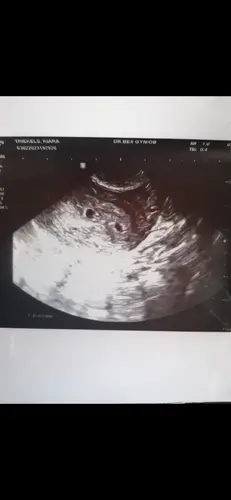

Dit was onze echo. Die cirkel is de dooierzak.Ik ben heel benieuwd hoe de volgende echo eruit ziet